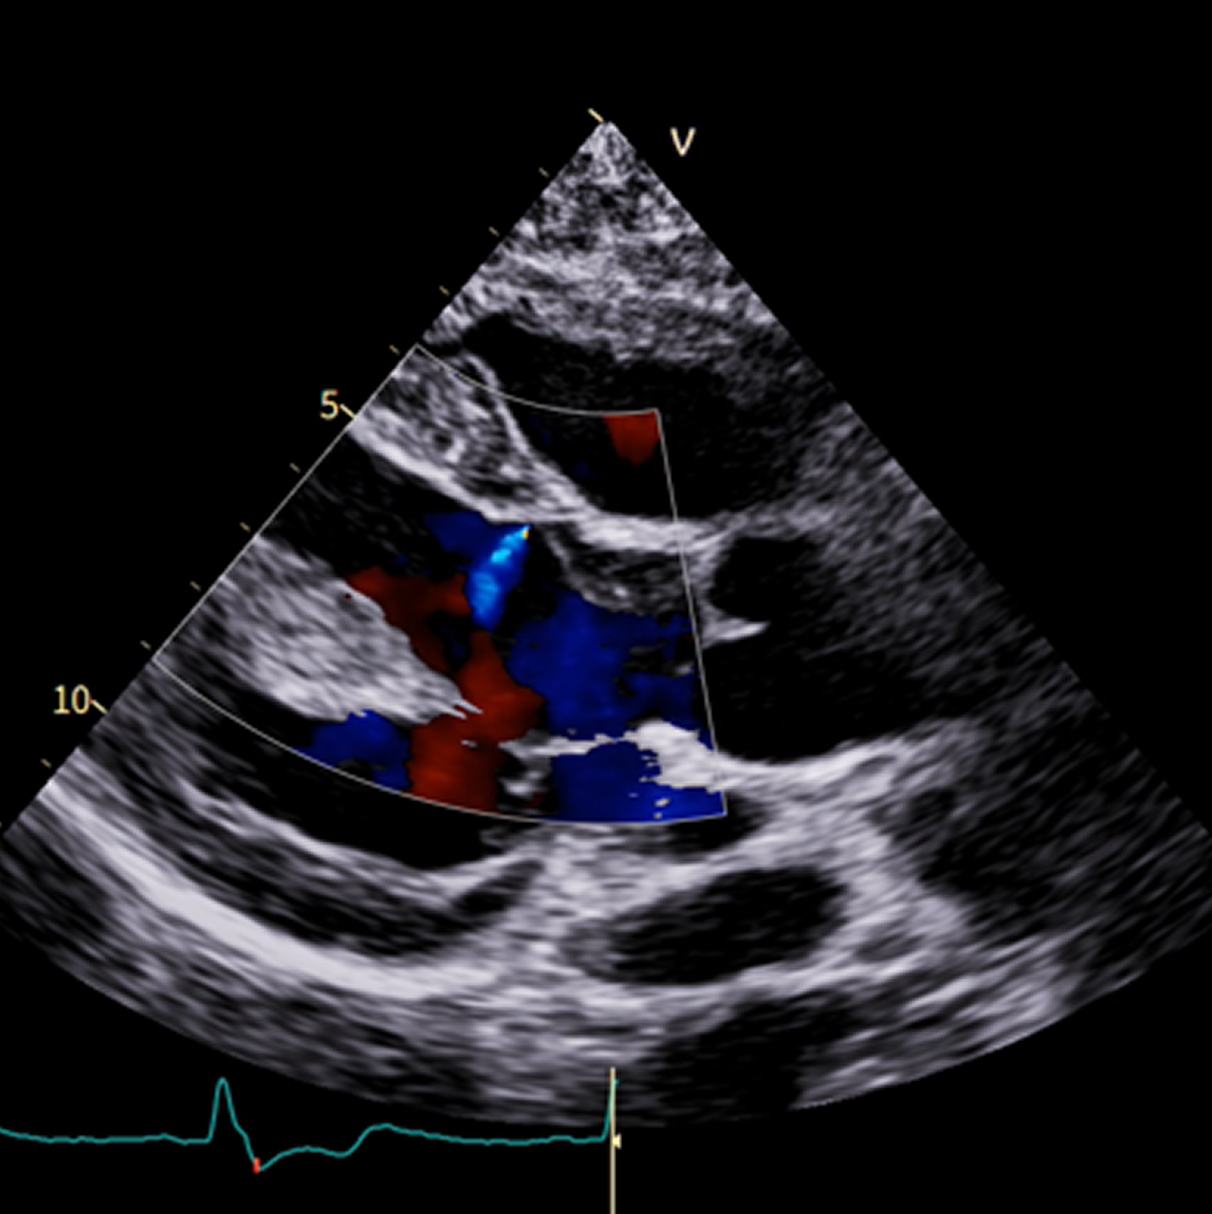

Caso condiviso da Marcello De Santis